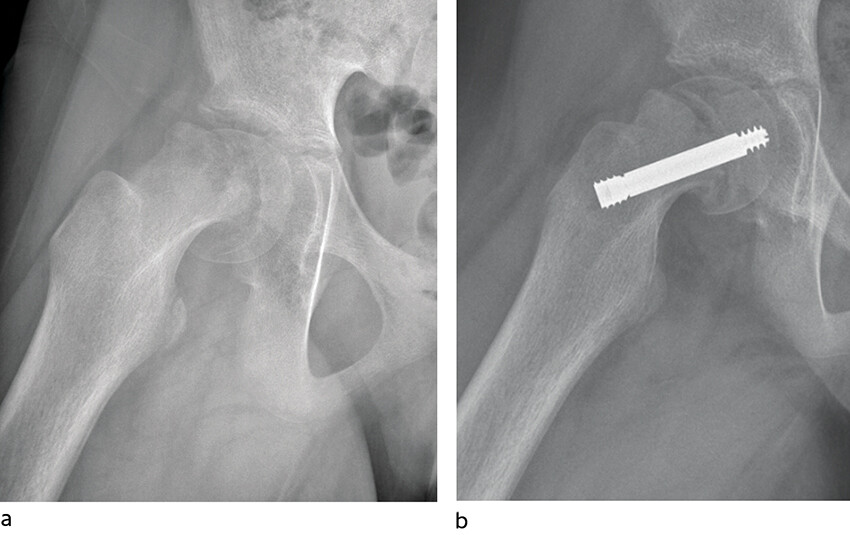

Standard behandling er operativ stabilisering av epifyseskiven. Hensikten er å gjøre pasienten symptomfri samt hindre ytterligere glidning. Epifyseskiven stabiliseres in situ, det vil si man gjør ingen forsøk på å reponere glidningen. Imidlertid vil en del av feilstillingen kunne reponere seg spontant ved ustabil epifysiolysis capitis femoris i forbindelse med leiring under operasjon (figur 2). Grunnen til at det ikke skal gjøres noe aktivt forsøk på reponering er at det gir økt risiko for skade på blodforsyningen til epifysen, med fare for caputnekrose som komplikasjon (11).

Dagens kliniske klassifikasjon skiller mellom stabil og ustabil epifysiolysis capitis femoris. Hvis pasienten klarer å vektbelaste med eller uten krykker, klassifiseres glidningen som stabil, og hvis pasienten ikke klarer å vektbelaste, er det en ustabil glidning (8). Radiologisk måles graden av glidning på sidebilde (figur 4). Glidning på < 30° klassifiseres som lett, 30–50° som moderat og > 50° som betydelig.